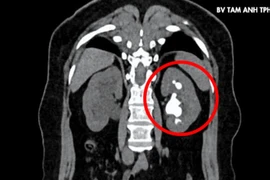

Lấy sỏi san hồ lấp đầy đài bể thận cho người phụ nữ 51 tuổi

Do kích thước lớn, cấu trúc phức tạp nên sỏi san hô không thể tự đào thải theo đường tự nhiên, có trường hợp trải qua nhiều lần phẫu thuật mới làm sạch sỏi.